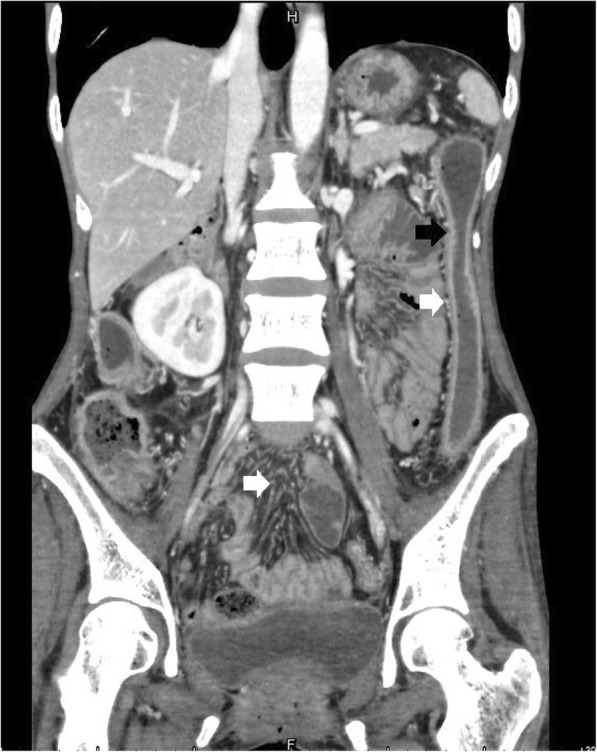

Fig. 3.

Coronal CTE of UC showed loss of haustration, lumenal narrowing, mucosal hyperenhancement (black arrows) and engorgement of mesenteric vessels (white arrows)

Of the total 46 cases, bowel wall thickening was seen in 43 cases (Figs. 1, 2, 3, 4). Mural hyperenhancement was observed in 45 cases (Figs. 1, 2, 3, 4). Mural stratification was present in 21 cases (Figs. 1, 2, 4). Mucosal bubbles were present in 30 cases (Fig. 1). Loss of haustration was identified in 28 cases (Fig. 3). Mesenteric hyperemia was present in 23 cases (Figs. 2, 3, 4). Perirectal stranding was seen in 14 cases (Fig. 2). Lymph node enlargement was present in 19 cases. Intestinal pseudopolyps were identified in five patients (Fig. 4). Luminal narrowing was seen in 12 cases (Fig. 3).